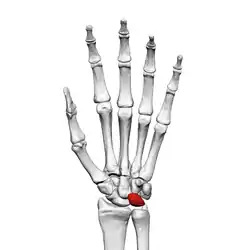

![]() Left hand anterior view (palmar view). Lunate bone shown in red. | |

The lunate bone (semilunar bone) is a carpal bone in the human hand. It is distinguished by its deep concavity and crescentic outline. It is situated in the center of the proximal row carpal bones, which lie between the ulna and radius and the hand. The lunate carpal bone is situated between the lateral scaphoid bone and medial triquetral bone.

The lunate is a crescent-shaped carpal bone found within the hand. The lunate is found within the proximal row of carpal bones. Proximally, it abuts the radius. Laterally, it articulates with the scaphoid bone, medially with the triquetral bone, and distally with the capitate bone. The lunate also articulates on its distal and medial surface with the hamate bone.[2]: 708 [3]

The carpal bones function as a unit to provide a bony superstructure for the hand.[2]: 708 As a proximal carpal bone, the lunate is also involved in movement of the wrist.[3]

The lunate bone is the most frequently dislocated carpal bone.